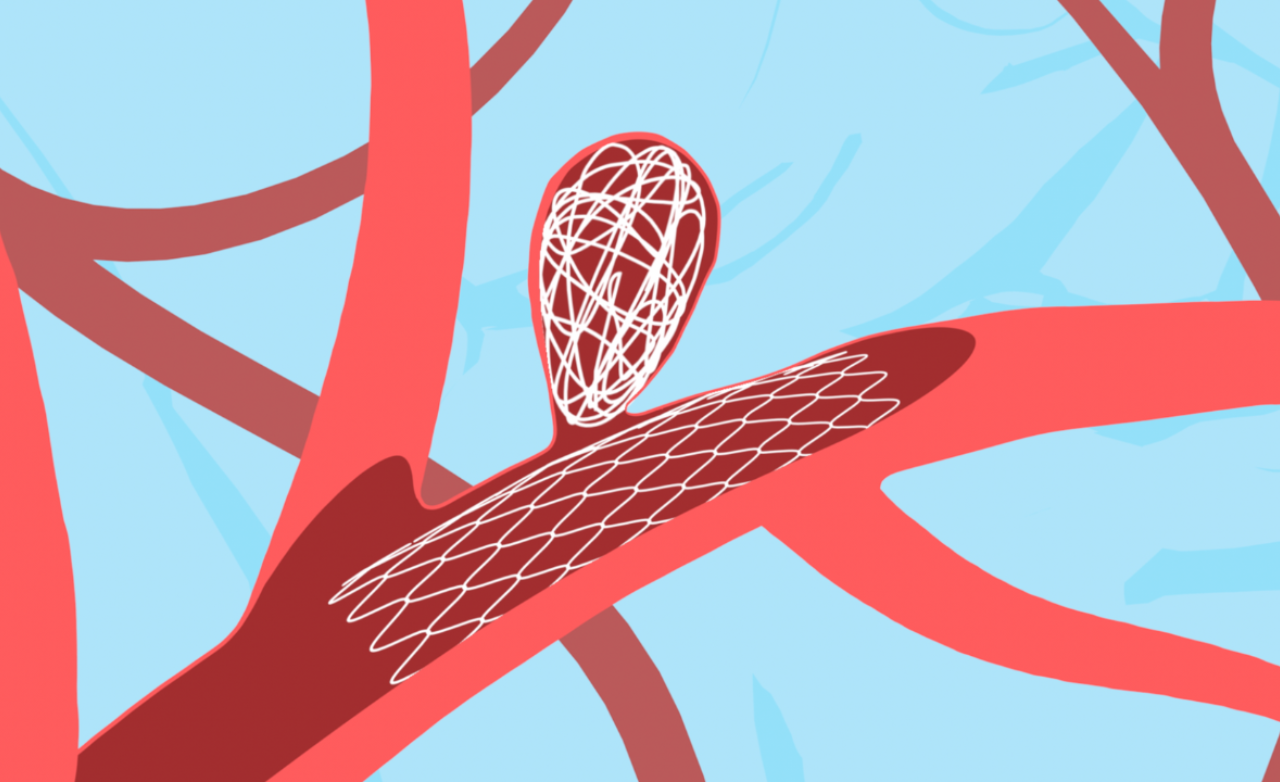

Stent or balloon assisted coiling is used for wide-neck brain aneurysms where simple coiling is unsafe or insufficient. These techniques support the aneurysm neck during treatment.

They help keep coils securely in place, prevent coil movement, and improve long-term aneurysm sealing safely.

Intrasaccular devices are placed directly inside the aneurysm sac to block blood flow at its origin. They are useful for select wide-neck aneurysms.

These devices seal the aneurysm internally without affecting the parent artery or surrounding brain circulation.